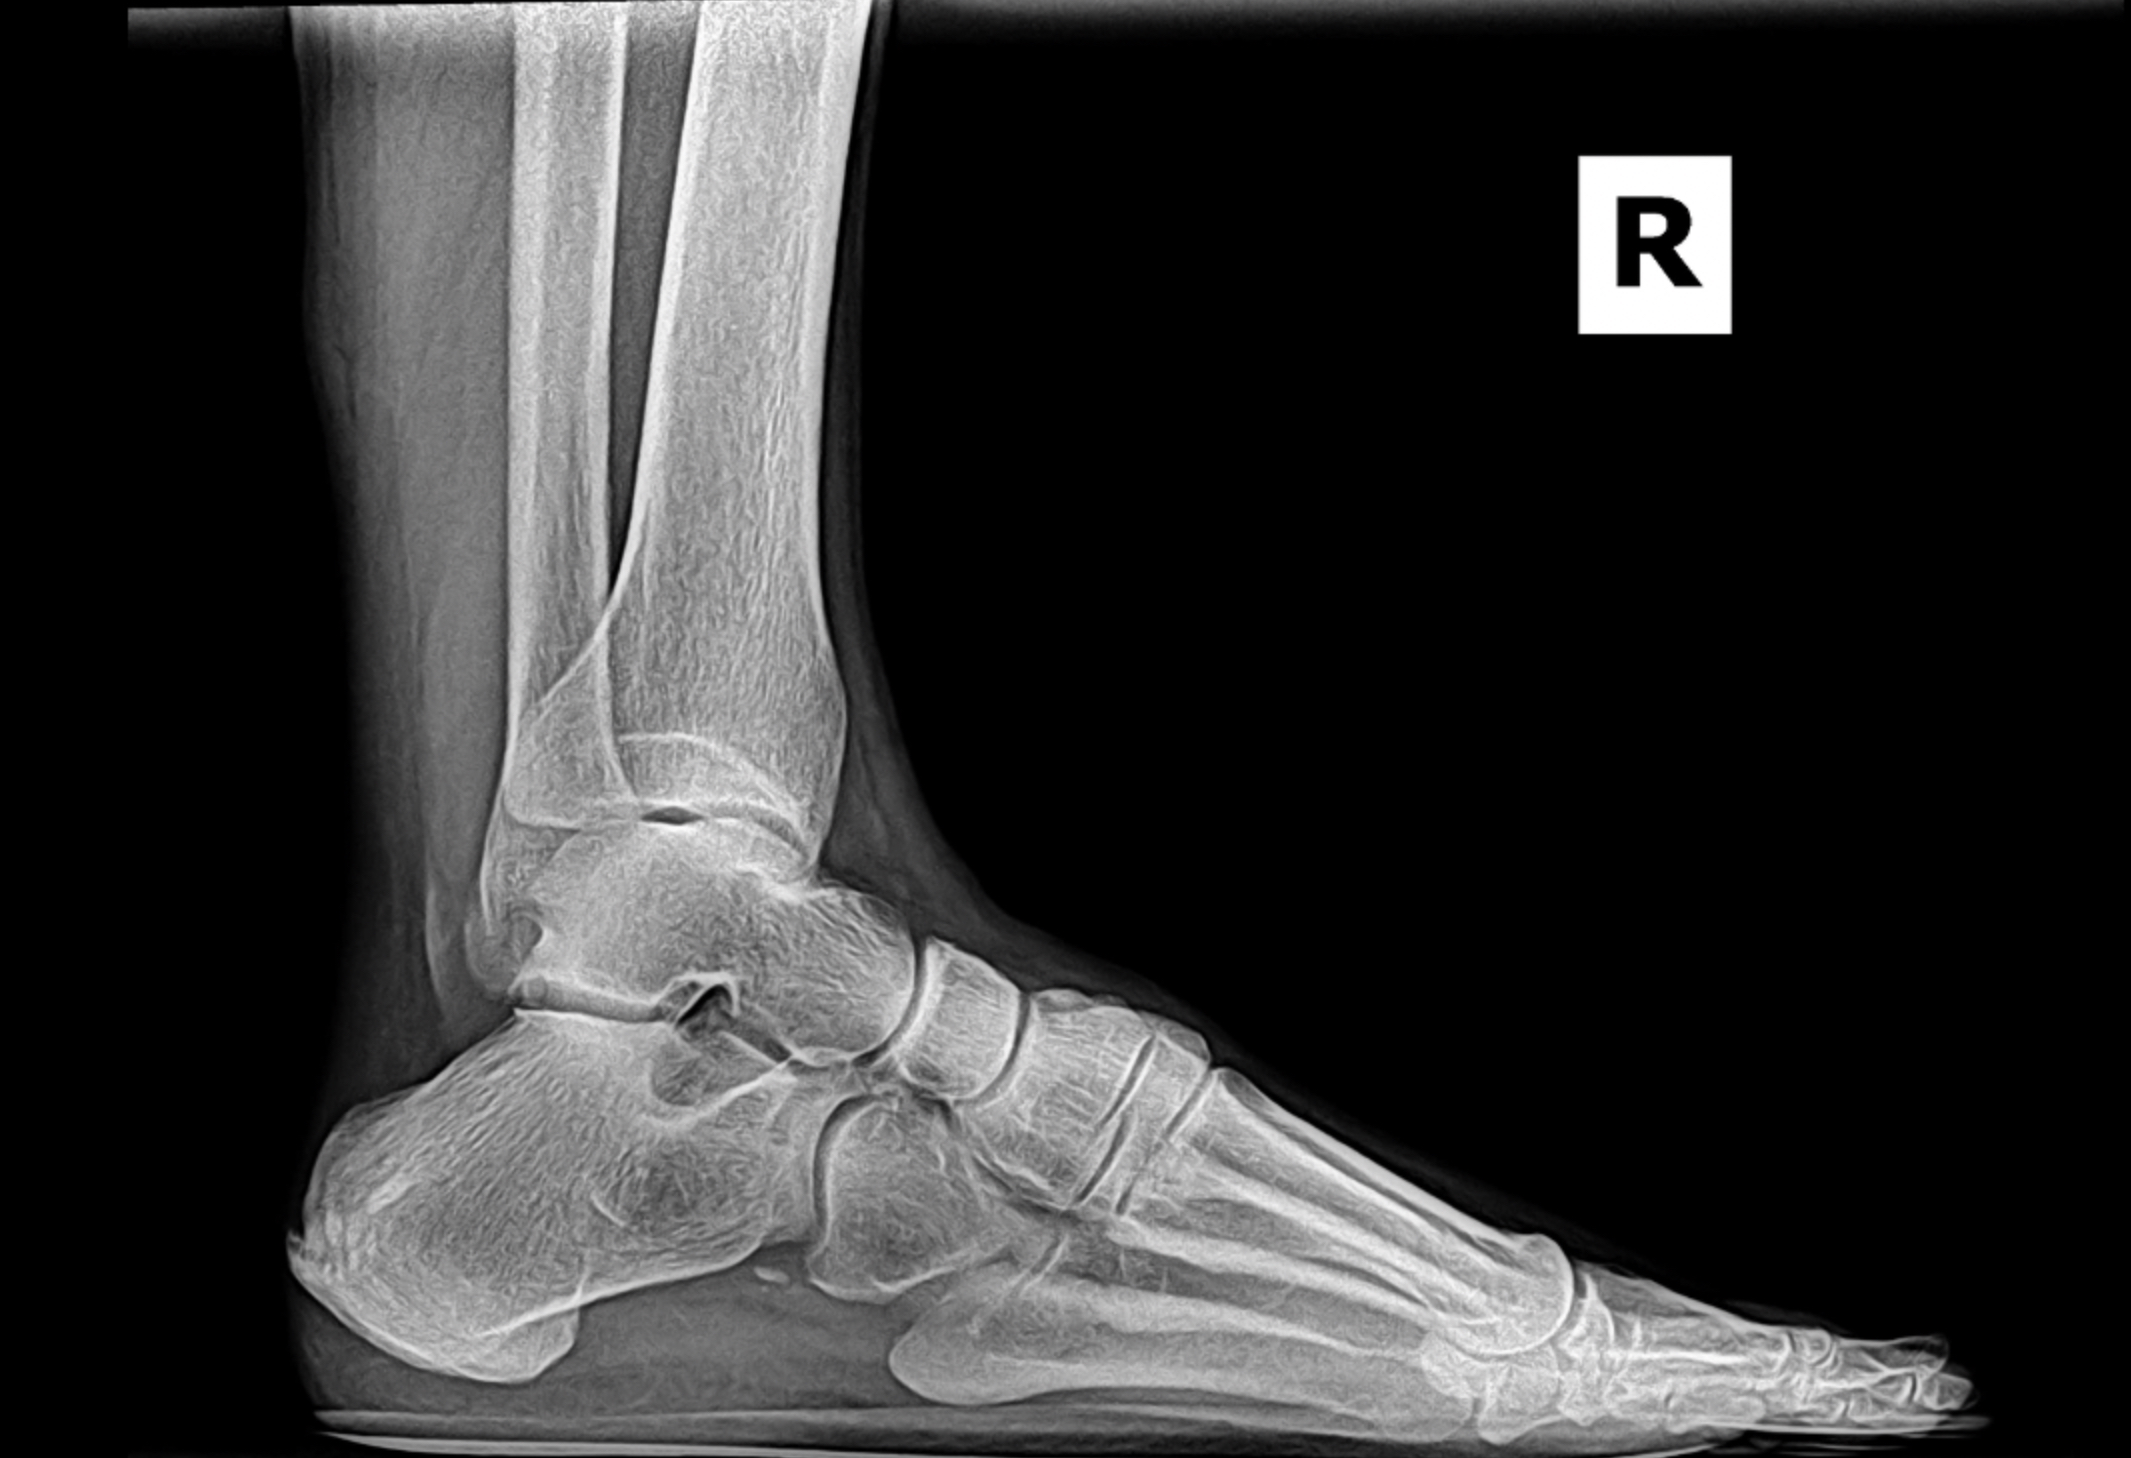

Pre-op XR Images